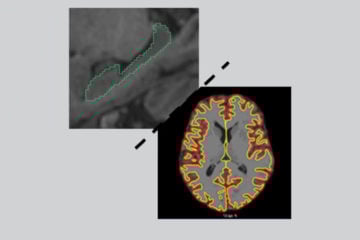

Sciences participatives : analyser des images IRM pour faire avancer la science

Published on 12 May 2021

Les 25 et 26 mai, par la plateforme de découverte scientifique SPINE